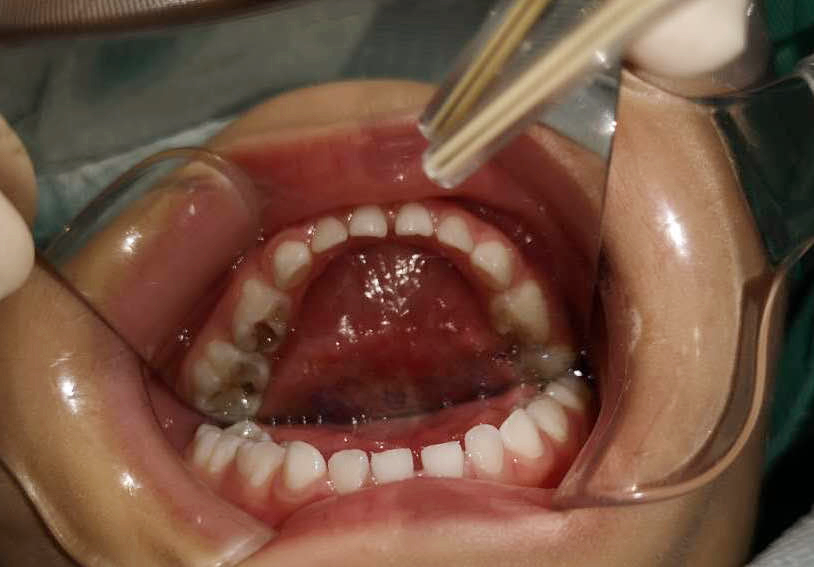

齲齒充填、根管調(diào)節(jié)、窩溝封閉......西海岸新區(qū)中心醫(yī)院的兒童口腔醫(yī)生丁彬主治醫(yī)師和申家麗住院醫(yī)師有條不紊地進(jìn)行著操作,劉亞芳醫(yī)師、李雪飛醫(yī)師和高聰醫(yī)師在旁邊配合著操作,一切井然有序,只有儀器發(fā)出“嘀、嘀”的聲音,提醒著時(shí)間的流逝。

丁彬醫(yī)師和申家麗醫(yī)師正在為小患者進(jìn)行全麻下牙齒調(diào)節(jié)

兩個(gè)多小時(shí)后,這一多達(dá)8顆患牙的復(fù)雜調(diào)節(jié)順利完成。在這期間,鑫鑫的心率和血壓一直被密切監(jiān)測(cè)著,一切都很正常。

調(diào)節(jié)前

調(diào)節(jié)后